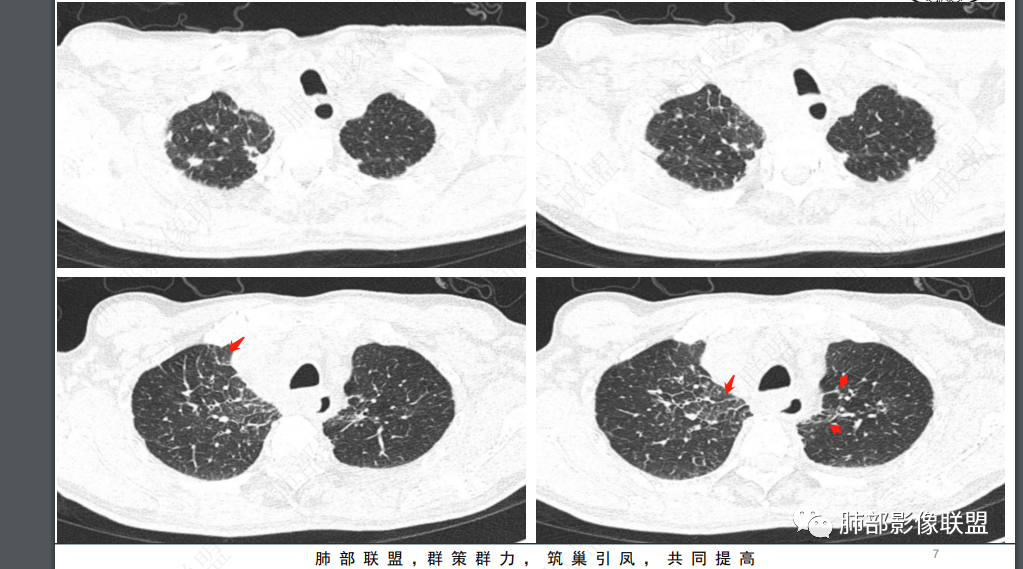

2、影像特点:双肺多发结节及条索影,边缘清晰,右肺上叶可见网格影,右侧胸腔少量积液;颈部、纵膈及腹部多发淋巴结肿大,大部淋巴结强化不均,呈环形强化,内部见低密度坏死区,部分淋巴结坏死不明显,尤其是腹部淋巴结密度较均匀。